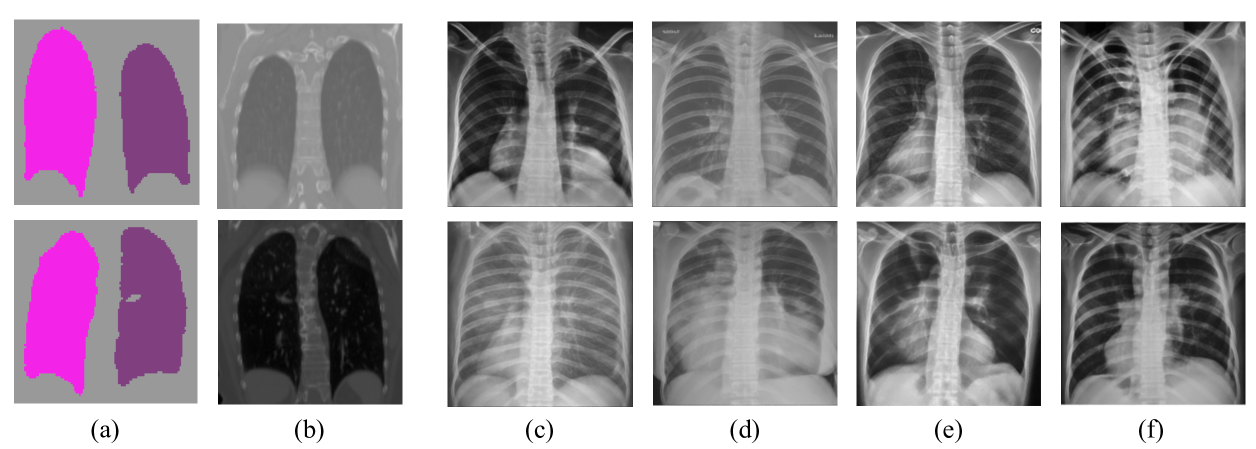

We also visualize the segmentation results of our method and other DG approaches for all tasks in Fig. 3Fig. 4 and Fig. 5, respectively. The first two columns show source and target domain images, illustrating the domain shift. We can see that the segmentation masks in the unseen target domain produced by our method exhibit greater accuracy and improved spatial continuity of the foreground compared to the baselines.

\begin{overpic}[width=216.81pt]{Figs/WACV_fig5.pdf} \put(2.8,0.5){\color[rgb]{0,0,0}\tiny{Source}} \put(15.25,0.5){\color[rgb]{0,0,0}\tiny{Target}} \put(25.0,0.5){\color[rgb]{0,0,0}\tiny{MixStyle}} \put(35.1,0.5){\color[rgb]{0,0,0}\tiny{RandConv}} \put(46.1,0.5){\color[rgb]{0,0,0}\tiny{DualNorm}} \put(58.5,0.5){\color[rgb]{0,0,0}\tiny{CSDG}} \put(69.25,0.5){\color[rgb]{0,0,0}\tiny{SLAug}} \put(81.0,0.5){\color[rgb]{0,0,0}\tiny{Ours}} \put(89.0,0.5){\color[rgb]{0,0,0}\tiny{Ground Truth}} \end{overpic}

Figure 5: Visualization of segmentation results on the LS task. First two rows: “CT to X-Ray”.